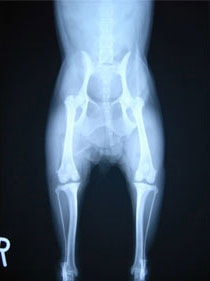

内方膝蓋骨脱臼の発生原因は内反股と大腿骨頸の前捻であると結論づけている研究があります。また、遺伝的要素が重要と考えられており、大腿四頭筋機構の異常、股関節異常、後肢の変形との関連などが報告されておりますが、現在でも正確な病因あるいは発生機序は分っておらず、治療方針や合併症の問題に関して議論が続いています。10kg以下の小型犬に多く認められる傾向があること、大型犬でも内方への脱臼が全体の75~90%を占める傾向があります。